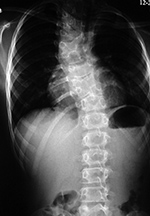

| Patient with severe spinal deformity treated by expandable rib devices |

| Young child with congenital spinal anomaly and progressive scoliosis. Two expandable ribs were placed to stabilize and reduce the scoliosis. |

TIS devices devices are designed for skeletally immature patients who have severe, progressive spinal deformity or thoracic deformity and who are at risk for developing thoracic insufficiency syndrome in which the thorax and spine cannot support normal respiration or lung growth. This includes patients with progressive congenital, neuromuscular, or idiopathic scoliosis (figure: congenital spinal deformity and expandable ribs). Such devices expand the rib cage or slow progressive deformity of the thorax by mechanically stabilizing the thorax and distracting a portion of the rib cage. TIS apparatus consists of rib to rib, rib to spinal lamina, or rib to pelvis expandable bars which can adjust to patient growth (figure: TIS devices). There is limited experience with the use of expandable ribs and similar devices. There does seem to be a high rate of complications, and it is possible many patients with congenital scoliosis may do well with advanced bracing rather than spinal or thoracic cage surgery (Weiss, 2016).